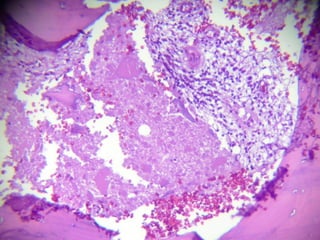

• SE REALIZA LAPE, REPORTÁNDOSE: MÚLTIPLES

IMPLANTES PERITONEALES EN TODA LA

CAVIDAD Y ÓRGANOS INTRAABDOMINALES,

INTESTINO DELGADO ACARTONADO CON

PUNTILLEO BLANQUECINO, EN TODA SU

SUPERFICIE.

• CON TUMORACIÓN Y ESTENOSIS DE LA LUZ A

250 CM DE ASA FIJA. SE OBSTRUYE CASI EL

90% DE LA CIRCUNFERENCIA.

• TUMOR DE CIEGO DE 5 X 5 X 5 CM QUE

OBSTRUYE MÁS DE 90% DE LA LUZ. SE

REALIZA RESECCIÓN ENTERO-ENTERO-

ANASTOMOSIS TERMINO- TERMINAL,

HEMICOLECTOMÍA DERECHA E ILEOSTOMÍA

MÁS LAVADO Y SECADO DE CAVIDAD.

• SE ENVÍAN AL SERVICIO DE PATOLOGIA LAS

MUESTRAS ENCONTRÁNDOSE HALLAZGOS

COMPATIBLES CON TBC.

 COLON DERECHO QUE MIDE 20 CM DE

LONG, EL ILEON TERMINAL MIDE 10 CM Y

EL APÉNDICE CECAL 9 CM DE LONG. SE

OBSERVA DILATACIÓN A NIVEL DE LA

VÁLVULA ILEOCECAL DE 10 X 8 CM. AL

CORTE LA PARED ESTÁ ENGROSADA Y

MIDE 1 CM DE ESPESOR, LOS PLIEGUES DE

LA MUCOSA ESTÁN BORRADOS.

 LA RESECCIÓN SEGMENTARIA DE ILEON

MIDE 68 CM DE LONG. LA SEROSA

MUESTRA LESIONES BLANCAS

MILIMÉTRICAS Y A 0.6 CM DEL LÍMITE

QUIRÚRGICO SE IDENTIFICA UNA

CONSTRICCIÓN DE LA LUZ. LOS LÍMITES

QUIRÚRGICOS ESTÁN LIBRES DE LESIÓN

( A 6 CM ) EL EPIPLÓN MIDE 20 CM Y

PRESENTA UN NÓDULO DE 2 CM DE

DIÁMETRO.

 TUBERCULOSIS INTESTINAL Y PERITONEAL